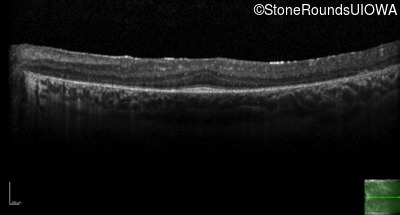

Optical Coherence Tomography - Right - 20/40 -1 sc

Exemplar / OCT Stack

OCT Stack

Optical Coherence Tomography - Left - 20/32 sc